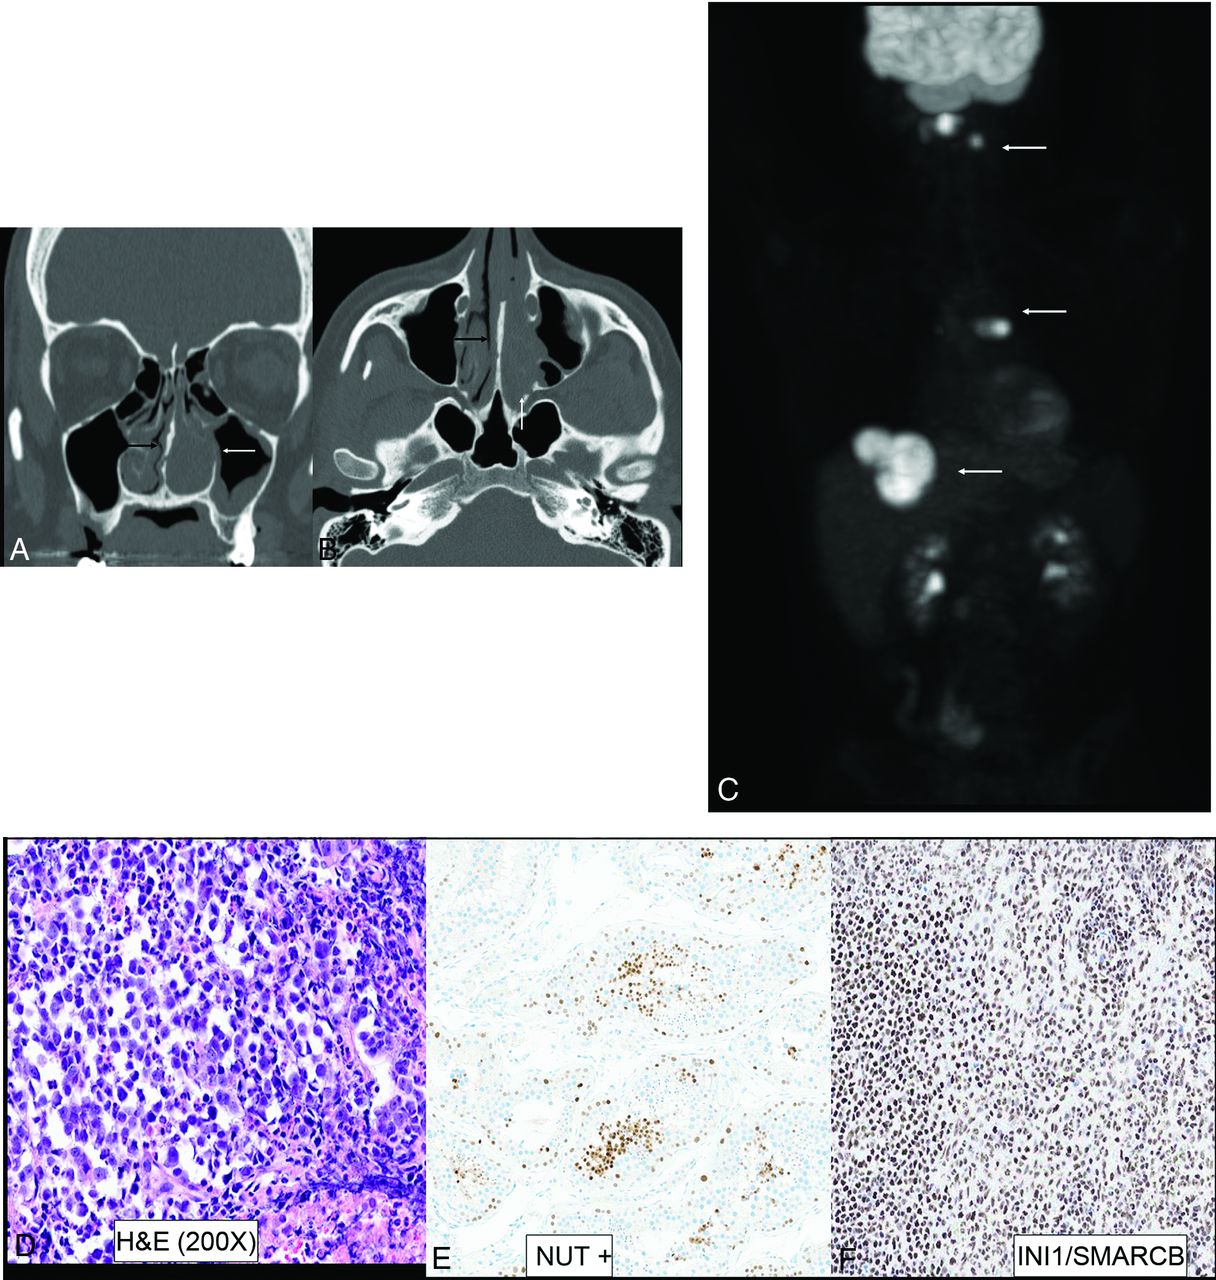

NUT carcinoma was a new entity in the previous (4th) edition and is better defined in the current 5th edition.1 It was previously called NUT midline carcinoma due to proclivity for midline sites. NUT carcinoma has been recognized in up to 18% of upper aerodigestive tract poorly differentiated carcinomas, with recognition aided by improved testing techniques and increased availability of commercial antibodies. The defining genetic feature of NUT carcinomas includes fusion of the NUTM1 gene, most commonly to BRD4.20 There are <100 cases described in the literature, limiting detailed description of imaging features. Limited series and published case reports have described aggressive imaging findings, like those in the mediastinum, with bony hyperostosis, internal mineralization, avid contrast enhancement, and high FDG uptake (Fig 5).8,21 Other tumors in this category include sinonasal lymphoepithelial carcinoma, teratocarcinosarcoma, and SNUC. However, with advancement in molecular markers and identification of newly defined entities (eg, SWI/SNF complex–deficient sinonasal carcinomas), the diagnosis of poorly differentiated or undifferentiated entities like SNUC is becoming less common.1

NUT sinonasal carcinoma in a 22-year-old man. Left nasal cavity mass (A and B, white arrows) with hyperostosis of the septum (black arrows). Metastatic disease with lesions in the lymph nodes, liver, and lung (C, white arrows). H&E stain (D) shows sheets and nests of high-grade tumor cells with zones of tumor necrosis. The tumor exhibits positive staining on NUT immunohistochemistry (E) with preserved INI1 staining (F) (ruling out SMARCB1 deficiency). Genetic analysis revealed NUT-BRD4 fusion, the defining feature of NUT carcinomas.